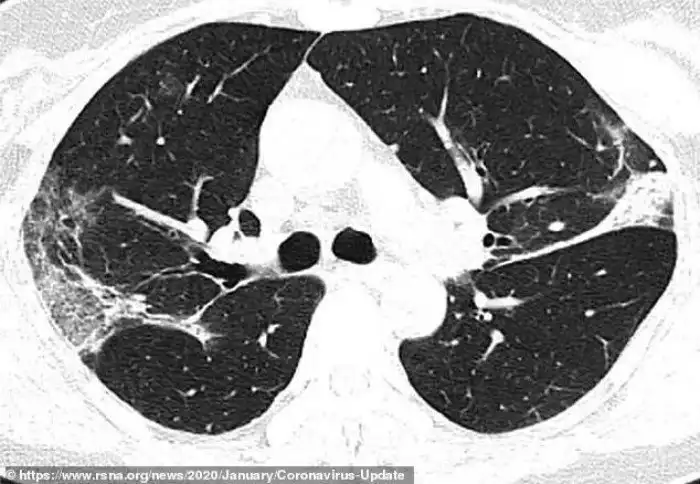

Это - снимок легких 45-летней женщины из Сычуани, протестированной после возвращения из Японии и диагностированной как носительница вируса. На снимке видно некоторое количество аналогичных образований, но здесь они сосредоточены в верхней доле левого легкого.